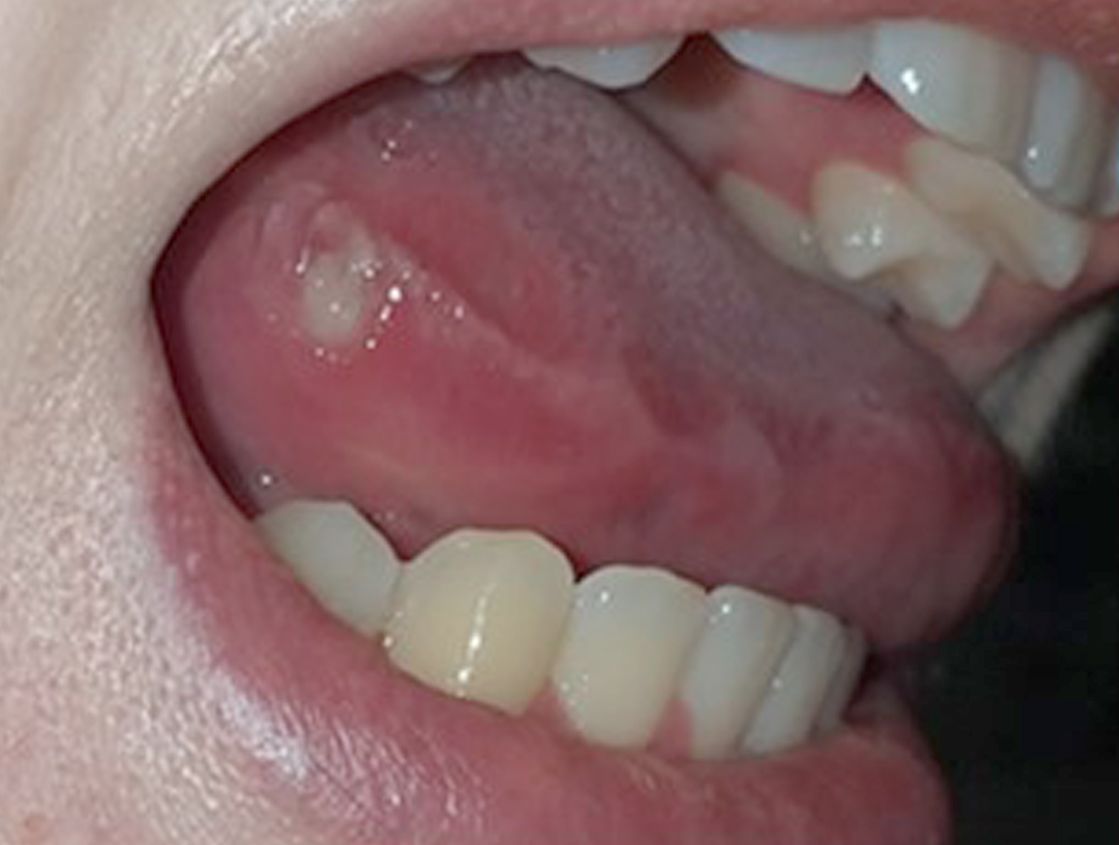

Aufnahme einer Aphthe an der Zunge

Orale Aphthe (Zungenrand)

• Orale Aphthen :

Bei oralen Aphthen handelt es sich um glatt begrenzte, zumeist querovale Geschwüre der Mundschleimhaut. Typischerweise finden sich Aphthen nicht nur im Bereich der Unterlippe, an den Wangenschleimhäuten und an der Zunge, sondern auch in den hinteren Abschnitten der Mundhöhle, sowie an Rachen und Gaumen.